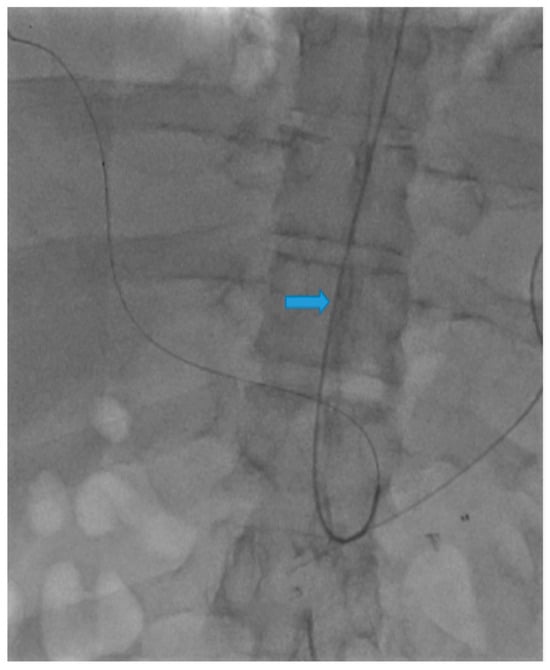

Use of Transradial Access to Install Two Sequential Stents for Pseudoaneurysms along the Celiac Artery and Common Hepatic Artery Axes